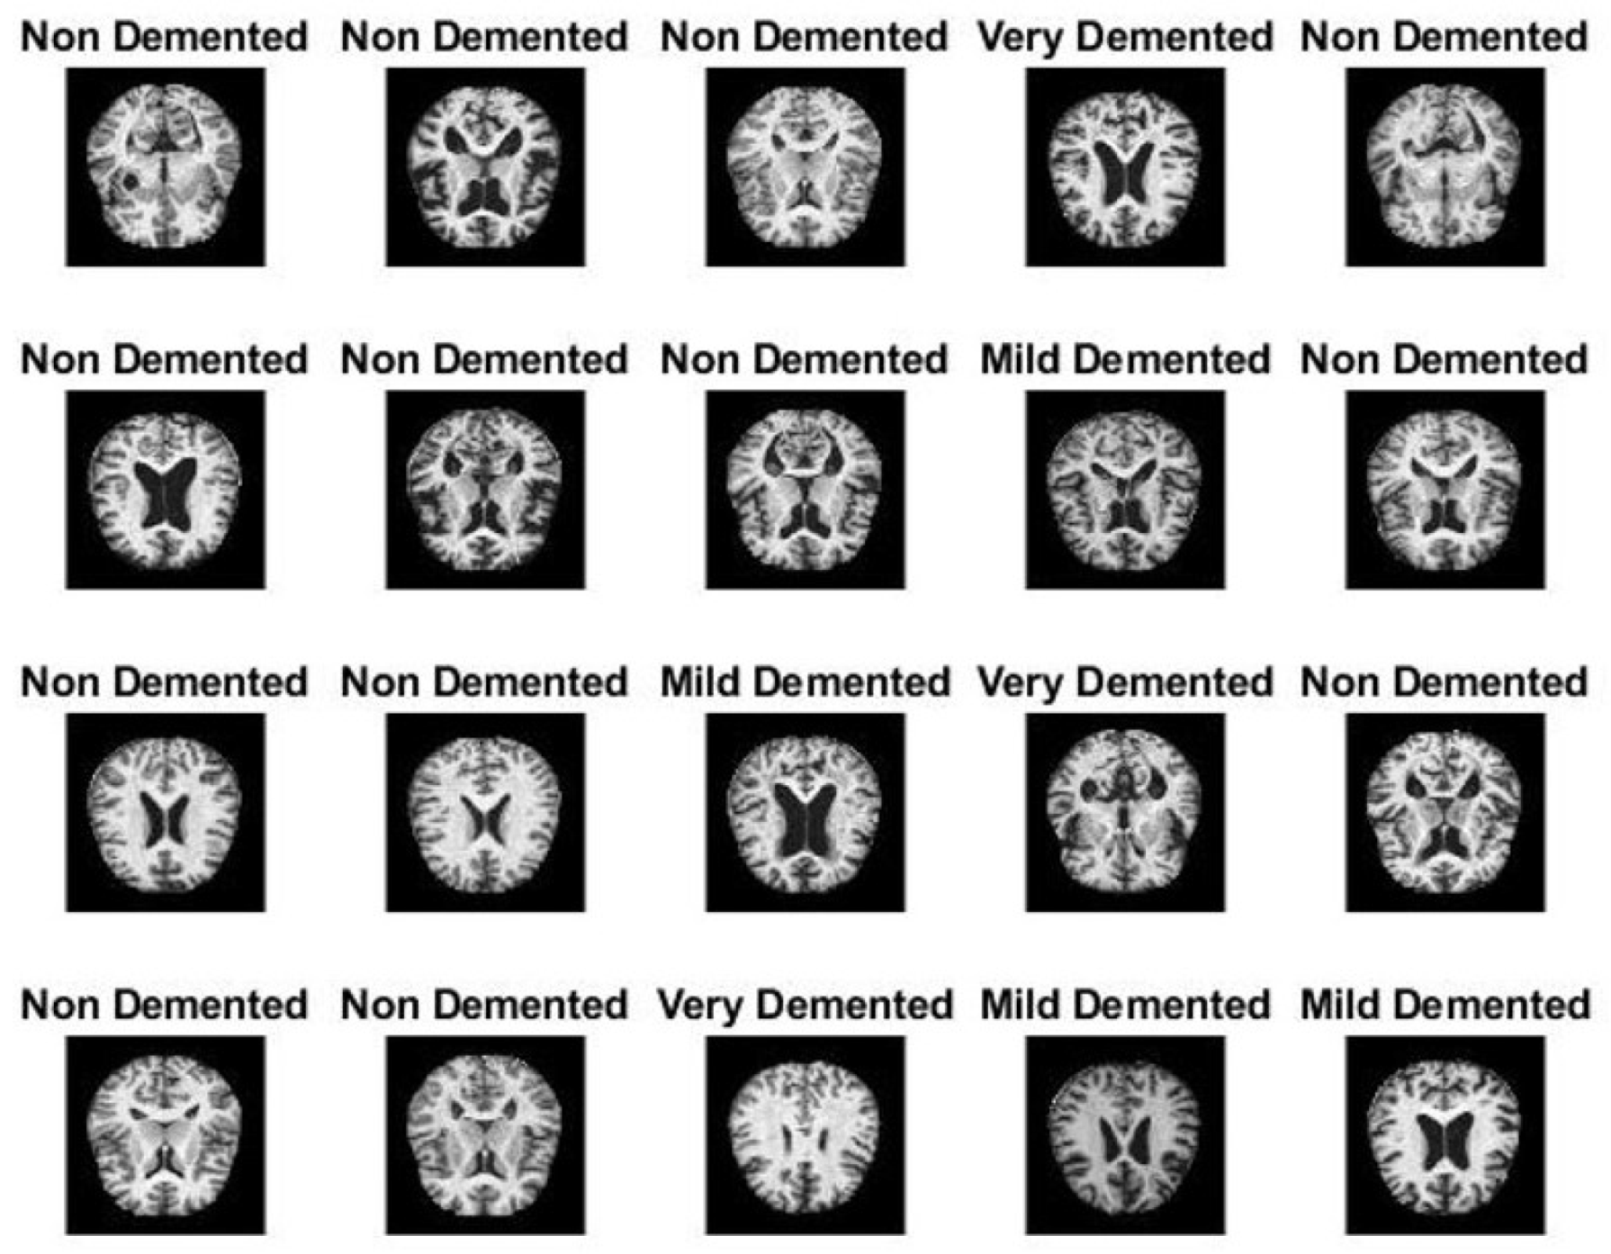

The MRI dataset for AD was obtained from the open source Kaggle website. The MRI dataset contains 6400 images separated into four classes, namely, mild dementia disease (896 images), moderate dementia disease (64 images), non-dementia (3200 images) and very mild dementia disease (2240 images) [29]. Figure 2 describes a sample of the MRI dataset for AD. https://www.kaggle.com/tourist55/alzheimers-dataset-4-class-of-images (accessed on 25 May 2021).

Figure 2. A sample of the MRI Alzheimer’s dataset.